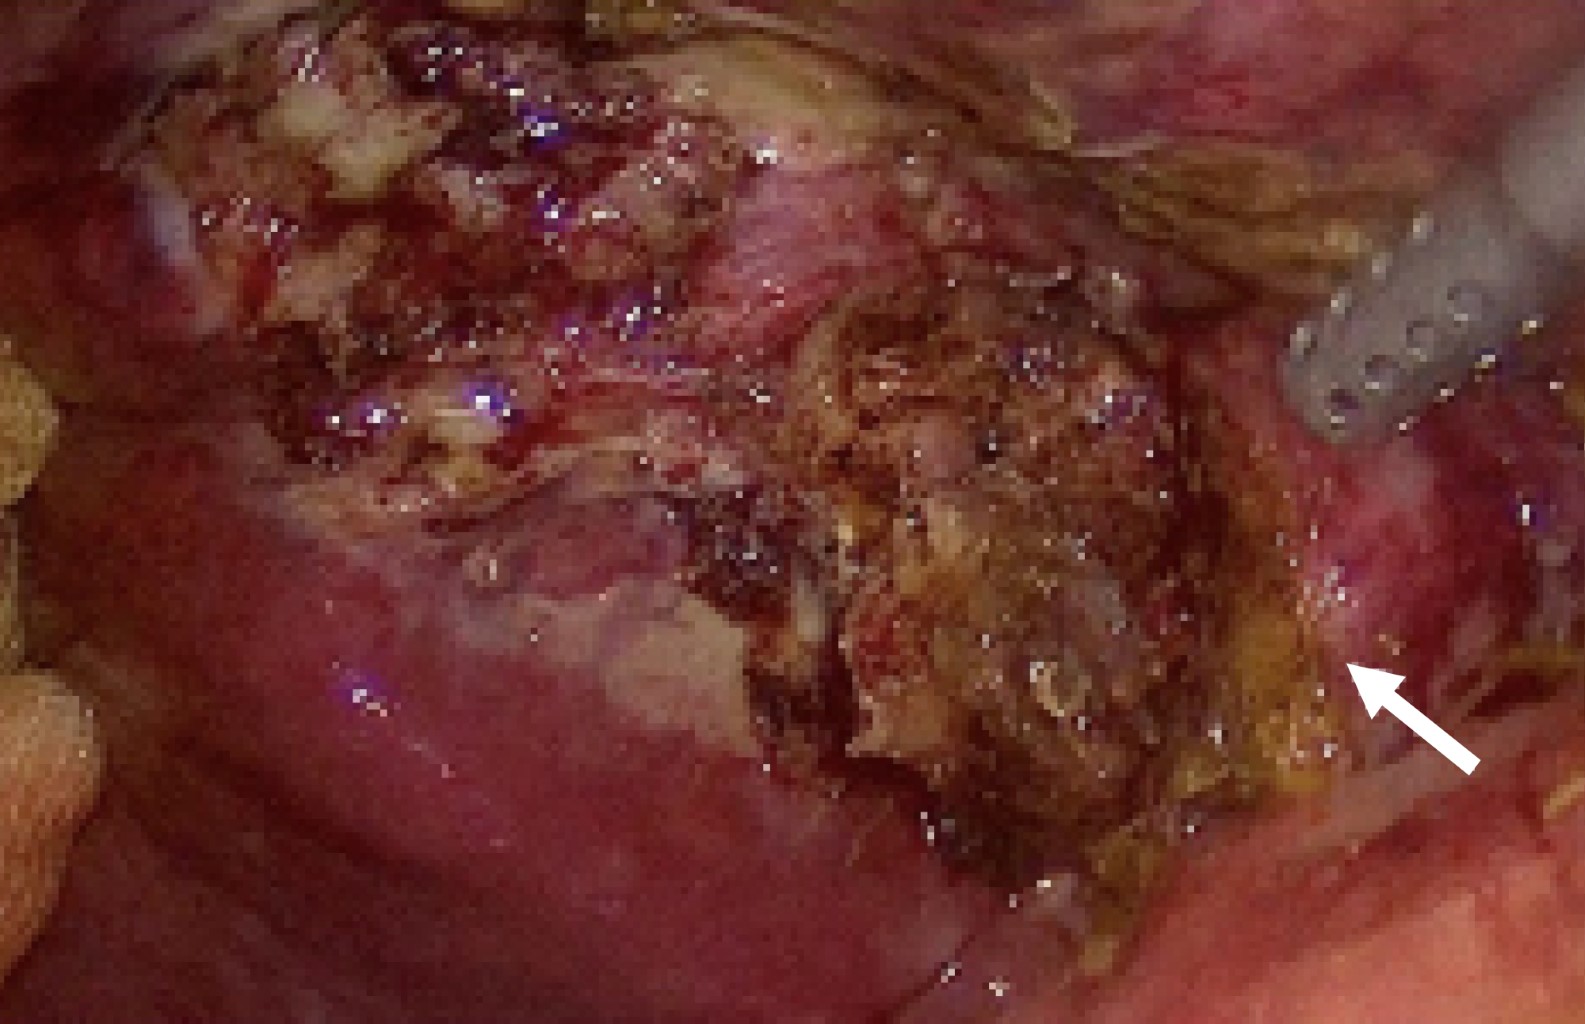

Introduction: the porcelain gallbladder represents a rare entity and it's associated with risk of malignancy. The treatment of choice is cholecystectomy, representing a surgical challenge given the degree of inflammation and fibrosis that this entity entails. Clinical case: we present a 56-year-old female with a history of recurrent episodes of biliary colic. She presents abdominal pain in the right hypochondrium of 7 hours of evolution, VNS (verbal numeric scale) 7/10 and nausea. Surgical treatment with laparoscopic cholecystectomy was decided. A gallbladder with a high degree of fibrosis, pearly color and adhesions to the omentum was found, a subtotal cholecystectomy was decided. Intraoperative retrograde cholangiography shows bile leakage from cystic duct and stent placement is performed. Conclusion: porcelain gallbladder is a histopathological condition in which there is calcification that infiltrates the gallbladder tissue. Found in 95% of cases of gallbladder lithiasis and represents special difficulty by limiting the field of vision due to its high degree of fibrosis. The prognosis depends on the degree of inflammation and the presence of malignancy. This entity entails a diagnostic and surgical challenge where the use of safe surgical alternatives for the patient becomes primordial, the technical knowledge and use of subtotal cholecystectomy is necessary for every surgeon who plans to perform laparoscopic cholecystectomy.

Figure 3